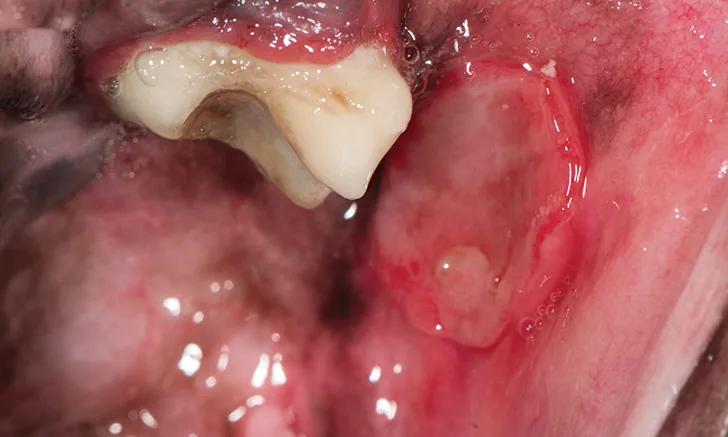

Round area of buccal mucosa ulceration adjacent to tooth.